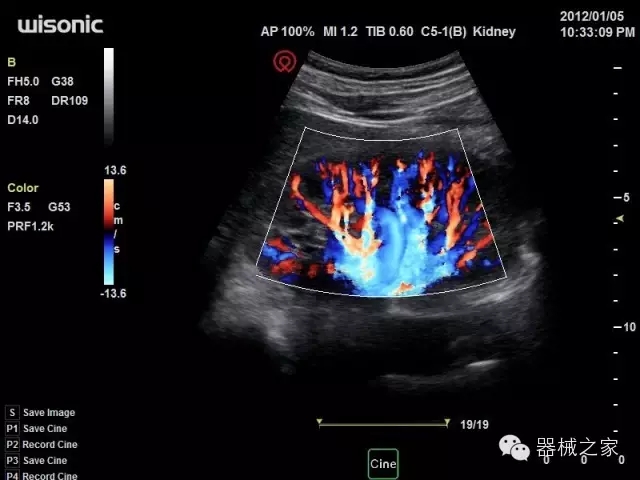

品牌:華聲醫(yī)療(WISONIC)

深圳華聲醫(yī)療技術(shù)有限公司成立于2012年,位于深圳南山西麗湖畔。是一家從事醫(yī)療設(shè)備研發(fā)、制造、營(yíng)銷的新興高新技術(shù)企業(yè),目前提供生命信息支持、數(shù)字便攜彩超、移動(dòng)醫(yī)療服務(wù)三個(gè)方面的業(yè)務(wù)解決方案。公司核心創(chuàng)始人均為醫(yī)療設(shè)備行業(yè)領(lǐng)軍人物,在醫(yī)療行業(yè)服務(wù)時(shí)間平均在10年以上,對(duì)行業(yè)和產(chǎn)品積累了深刻的認(rèn)識(shí)。公司在創(chuàng)立之初就有著長(zhǎng)遠(yuǎn)的戰(zhàn)略目標(biāo)和規(guī)劃,致力于醫(yī)療設(shè)備行業(yè)的細(xì)分市場(chǎng),貼近客戶所需,為大眾的健康提供更多關(guān)愛(ài)。

官方網(wǎng)站:www.wisonic.cn

經(jīng)典產(chǎn)品:四葉草

臨床圖片賞析

產(chǎn)品特點(diǎn)

·全球目前唯一一款配備主機(jī)雙探頭接口,整機(jī)重量(含電池)在5公斤以內(nèi)的便攜式彩超;

·一款互聯(lián)網(wǎng)彩超,只要有手機(jī)信號(hào)的地方就可以非常方便地實(shí)現(xiàn)遠(yuǎn)程會(huì)診和病案調(diào)取;

·鎂鋁合金外殼,堅(jiān)固可靠耐用;

·獨(dú)有的HoloTM PW 實(shí)時(shí)3取樣門PW成像技術(shù),精確進(jìn)行血管診斷;

·一鍵優(yōu)化B、Color、PW,Auto Doppler自動(dòng)識(shí)別血管位置、偏轉(zhuǎn)角度等,提高工作效率;

·30°超廣角精細(xì)偏轉(zhuǎn)成像技術(shù),更優(yōu)異的頻譜圖像;

·W+智能搜索引擎,快速尋找圖像;

·SSD、USB3.0保障開(kāi)機(jī)快,導(dǎo)出圖像更快,減少等待時(shí)間;

·WIFI、網(wǎng)口、3G,多重聯(lián)網(wǎng)方式,全天候保障云端備份,不再擔(dān)心圖像丟失;

CFDA注冊(cè)證編號(hào)

·粵械注準(zhǔn)201522231208